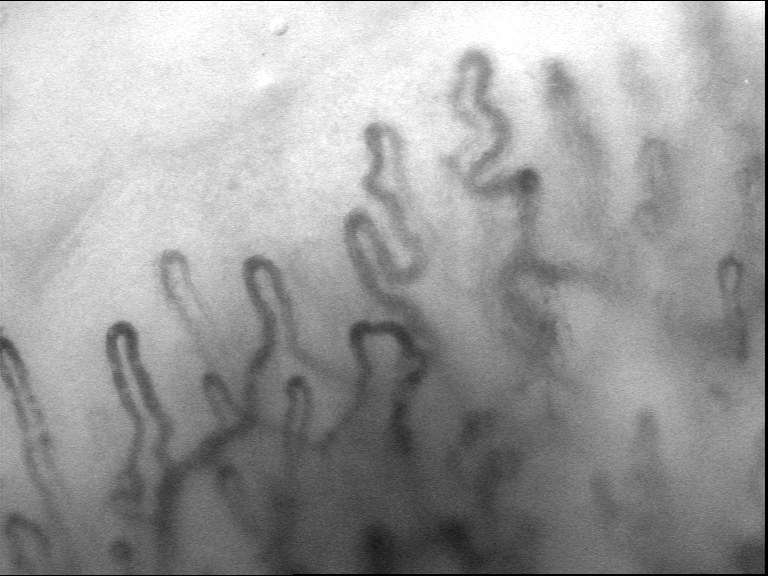

With movement correction using selected regions of the top layer small vessels.